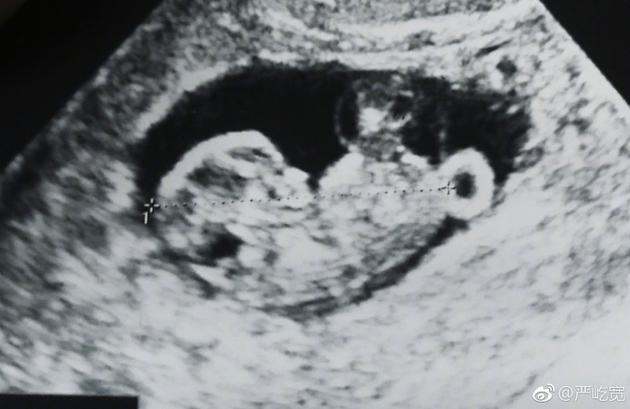

嚴屹寬曬出寶寶的B超照片

新浪娛樂訊 1月24日是嚴屹寬的生日,他在生日當天宣布了即將升級當爸的喜訊,并曬出了妻子杜若溪孕檢的照片,并發(fā)文感謝妻子,稱收到了“最好的生日禮物”。杜若溪隨后轉(zhuǎn)發(fā)為老公送上生日祝福。

24日早,嚴屹寬在微博曬出妻子孕檢的照片以及兩人的合照宣布妻子懷孕:“收到了最好的生日禮物,感謝我的肉肉”,并艾特妻子杜若溪本人的微博。隨后嚴屹寬將這條微博置頂。在三十九歲生日這天,嚴屹寬宣布妻子懷孕的消息并與網(wǎng)友們分享,一家人幸福滿滿,令人羨慕。